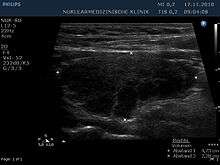

| The thyroid of someone with Hashimoto's thyroiditis as seen with a microscope at low magnification | |